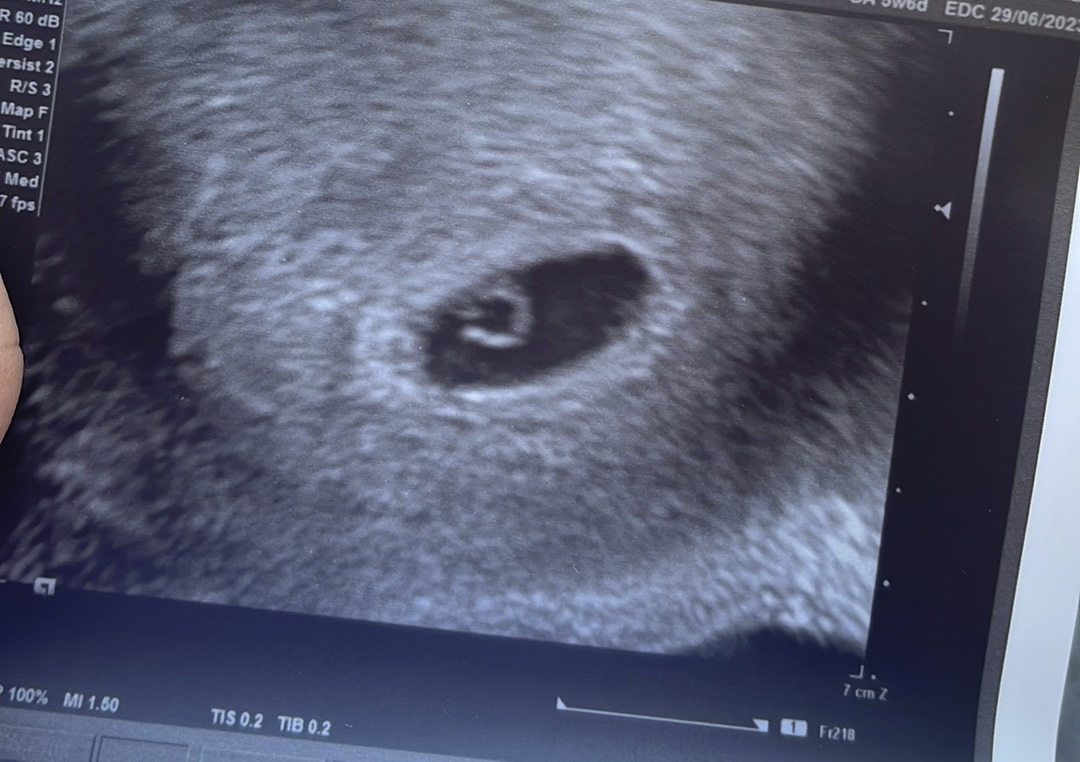

Tak nakoniec ten pepino test ktorý tu bol pred mesiacom bol falošný duch. Ale 22.10 kedy mala prísť menstruacia som robila testy a nakoniec som tehu 😅😅 bola som aj u lekára včera ale zatiaľ plod nevidno keďže podľa PM by som mala byt dnes v 6tt ale lekár povedal že som otehotnela niekedy v strede cyklu čiže napísal 4+5 tt. Uvidíme ako sa to bude postupne vyvíjať .